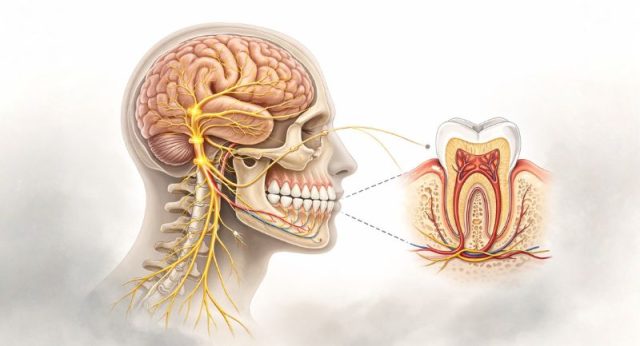

Dabei geht es nicht um einen Gegensatz zur bewährten zahnmedizinischen Versorgung, sondern um Ergänzung. Dein Mund ist Teil eines komplexen Regulationssystems. Nerven, Muskeln, Durchblutung und sogar deine Körperhaltung stehen mit deinen Zähnen in Wechselwirkung.

Dieser Ansatz betrachtet deinen Mund nicht als eigenständige Baustelle, sondern als Teil eines komplexen biologischen Systems. Deine Zähne stehen in Verbindung mit deinem Nervensystem, deinem Immunsystem, deiner Muskulatur und sogar mit deiner Körperhaltung.

Dein Mund ist kein abgeschlossener Raum. Er ist stark durchblutet, dicht von Nerven versorgt und eng mit deinem gesamten Organismus verbunden. Deshalb können Prozesse im Mundraum Auswirkungen auf deine Gesamtgesundheit haben, besonders dann, wenn sie über längere Zeit bestehen.

Auch dein Nervensystem ist eng eingebunden. Der Kiefer gehört zu den am stärksten innervierten Regionen deines Körpers. Dauerhafte Anspannung, Pressen oder Knirschen wirken nicht nur lokal. Sie können Spannungsketten auslösen, die sich bis in Nacken, Schultern oder Rücken fortsetzen.